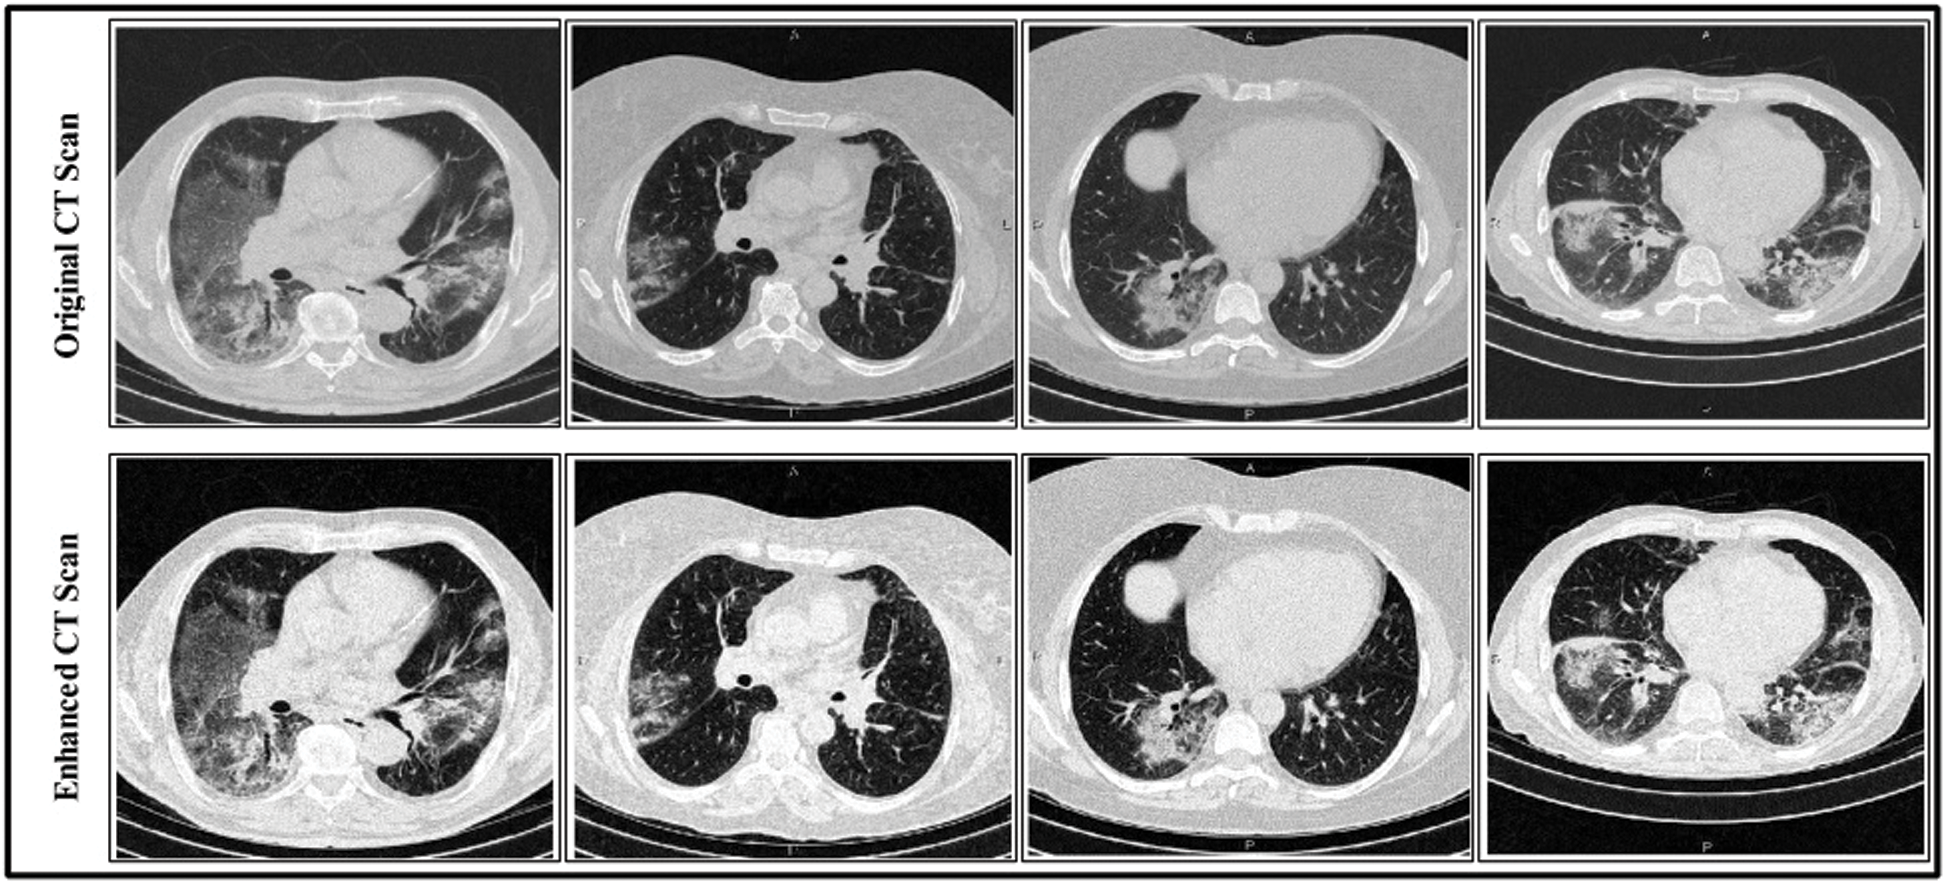

Contrast enhancement is an essential step in medical imaging that effectively increases the amount of visual information obtained from an image. The main objective of contrast enhancement in this work was to identify infected patients’ scans while distinguishing the most relevant features visually for a COVID-19 diagnosis. In this approach, a mean equation was used to improve the intensity range based on output. The mean value is computed mathematically as in Eq. (1):

, as shown in Fig. 3.

Figure 3: Linear contrast enhancement results